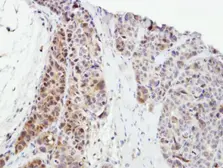

Images

Description

Applications